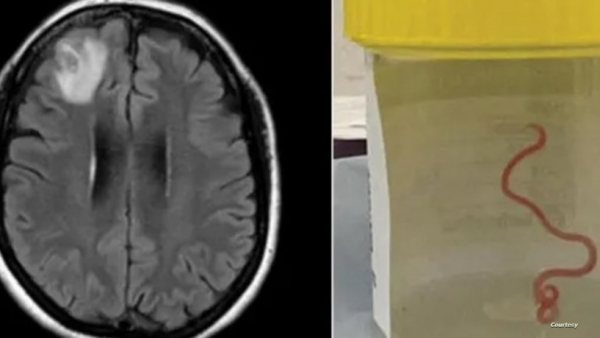

وسحبت جراحة الأعصاب، الدكتورة هاري بريا باندي، الدودة التي يبلغ طولها 8 سنتيمترات من المريضة، مما أصاب العاملين في المستشفى بالدهشة.

وعلى إثر ذلك، أدخلت مستشفى كانبيرا، حيث كشفت فحوص الرنين المغناطيسي لدماغها عن وجود تشوهات تتطلب عملية جراحية.

وعقد الفريق الطبي في المستشفى اجتماعا لمعرفة نوع الدودة، لكنهم لم يتمكنوا من تحديد ذلك، وتم إرسالها إلى أحد العلماء المتخصصين الذي أكد أنها دودة Ophidascaris robertsi التي تتواجد في الثعابين.